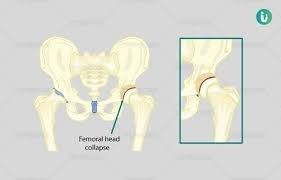

चिखली (Buldhana), ३० डिसेंबर २०२५: मलेशियात नोकरीनिमित्त वास्तव्य करणाऱ्या एका भारतीय व्यक्तीला गेल्या १८ वर्षांपासून कूल्ह्याच्या सांध्यातील असह्य वेदनांनी ग्रासले होते. डॉक्टरांनी त्यांना अव्हॅस्क्युलर नेक्रोसिस (AVN) असल्याचे सांगितले होते आणि शस्त्रक्रिया हाच एकमेव उपाय असल्याचे सांगितले. मात्र, आर्थिक अडचणी आणि उपचारांच्या खर्चामुळे त्यांनी वेदनांशी तडजोड करत आयुष्य जगणे पसंत केले. अखेर २०२५ मध्ये महाराष्ट्रातील चिखली येथील गंगाई हॉस्पिटलमध्ये आयुर्वेदिक उपचारांनी त्यांना अवघ्या ७ दिवसांत दिलासा मिळाला. हा अनुभव आयुर्वेदाच्या सामर्थ्याची एक प्रेरणादायी कथा आहे.

मलेशियात राहणाऱ्या या रुग्णाला १८ वर्षांपूर्वी कूल्ह्याच्या सांध्यात तीव्र वेदना सुरू झाल्या. अनेक नामांकित डॉक्टरांनी तपासणी केल्यानंतर AVN चे निदान झाले. “शस्त्रक्रिया व्यतिरिक्त दुसरा पर्याय नाही,” असे डॉक्टरांनी स्पष्ट केले. मात्र, घरची आर्थिक परिस्थिती साधारण असल्याने आणि शस्त्रक्रियेचा प्रचंड खर्च तसेच दीर्घकाळ उपचार परवडणारे नसल्याने रुग्णाने हा मार्ग टाळला. त्यावेळी AVN या आजाराबाबत फारशी माहिती उपलब्ध नव्हती. गुगल आणि यूट्यूबसारख्या प्लॅटफॉर्मवरही याबाबतचे अनुभव किंवा माहिती मर्यादित होती. परिणामी, रुग्णाने हा आजार आयुष्याचा भाग मानून स्वीकारला आणि वेदनांसह जगणे सुरू ठेवले.

मित्राने ही माहिती रुग्णाला दिल्यानंतर त्याने आपले सर्व वैद्यकीय रिपोर्ट्स ऑनलाइन पाठवले – चिखली येथील गंगाई हॉस्पिटल – आयुर्वेदिक पंचकर्म आणि संशोधन केंद्राकडे. डॉ. इंगळे यांनी रिपोर्ट्सचा सखोल अभ्यास केला आणि एक धक्कादायक निदान केले: “हा AVN नव्हे, तर हिप आर्थरायटिस आहे.” त्यानुसार, त्यांनी अवघ्या ७ दिवसांच्या विशेष आयुर्वेदिक थेरपीची शिफारस केली.

डॉ. इंगळे यांच्या मार्गदर्शनानुसार रुग्ण मलेशियातून थेट चिखलीला आला आणि उपचार सुरू केले. फक्त ७ दिवसांत वेदनांमध्ये लक्षणीय घट झाली, चालण्यात सुधारणा झाली आणि शस्त्रक्रियेविना उपचार शक्य असल्याचा आत्मविश्वास त्याला मिळाला. “१८ वर्षांच्या वेदनांपासून मुक्त होण्याची ही कल्पना स्वप्नवत वाटत होती,” असे रुग्णाने सांगितले (नाव गोपनीय ठेवण्यात आले आहे).